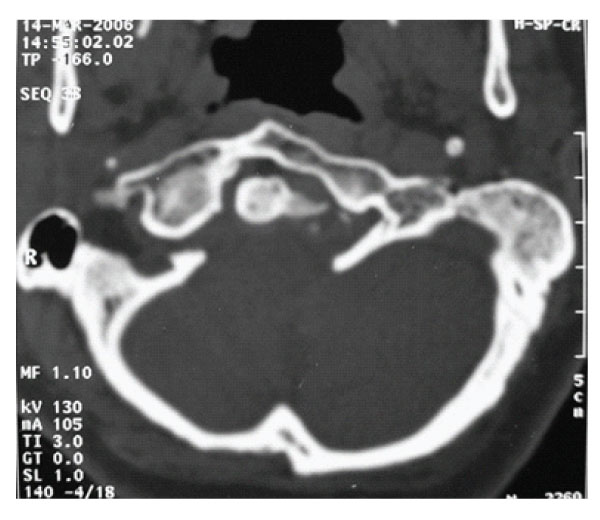

Figure 1: Axial slice of CT scan showing anterior assimilation of Atlas and asymmetric condyles.

X-ray examination disclosed no instability. Axial CT scans, three dimensional reconstructed CT scans and MRI showed anterior occipitalization of atlas, asymmetrical condyles with hypoplasia of left posterior part of the atlas, rightward deviation of odontoid process and C1-5 syringomyelia without tonsillar herniation [Figure- 1,2,3,4]. Posterior part of the axis was also asymmetrical. There was no appearance of basilar invagination although the tip of the axis was 2 mm superior to the foramen magnum level (McRae line).